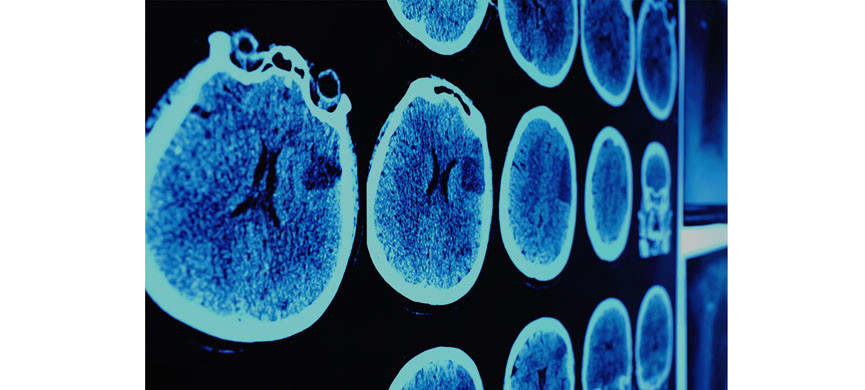

«Рак лечится как грипп»

В эксклюзивном интервью Jewish.ru известный московский онколог и главный специалист центра «Активмед» доктор Геннадий Рабаев объяснил, как обида вызывает рак, когда онкологические заболевания наконец победят и почему Уинстону Черчиллю повезло с генетикой.

Скажите как онколог, когда же будет изобретено лекарство от рака?

– Это, наверное, философский вопрос, потому что название одно, а заболеваний – много. Более того – биология опухоли одной и той же локализации со временем меняется. Возьмём рак молочной железы – один из самых распространённых видов онкозаболеваний. Рак в Центральном федеральном округе биологически может отличаться от рака на Дальнем Востоке. Или, например, рак предстательной железы 30 лет назад и сейчас – это в принципе два разных заболевания.

Прорыв в понимании изменчивости природы рака произойдёт за счет развития молекулярной биологии и генетики, благодаря которым стало возможно выявлять особенности изменения опухолей. Пока же сложно говорить о победе над раком. Возможно, когда-нибудь он будет побеждён в каком-то виде, а возможно, он сам изменится до такой степени, что войну нужно будет начинать сначала.

Какие виды рака сейчас точно лечатся?

– Раньше слово «рак» звучало как приговор. Сейчас достигнут ощутимый прогресс в лечении самых распространённых видов опухолей. Многие больные с раком предстательной железы живут более 10–15 лет, и это существенный прогресс в лечении. Пациентки с заболеванием молочной железы тоже в большинстве случаев поддаются лечению. А по тем заболеваниям, которые раньше мы не брались лечить, сейчас можно говорить о стабильных пятилетних результатах продолжительности жизни, когда болезнь не влияет на её качество. Появились новые препараты и, главное, пришло новое понимание, как живет опухоль с её биологией и клиническими особенностями.